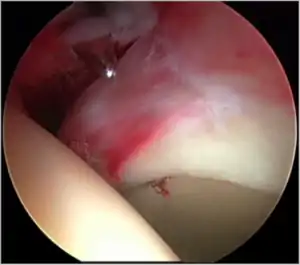

Figure 5. Portal placement under direct vision. The instrument is entering the joint through the hip capsule, between the femoral head (on the left) and acetabular labrum (on the right)

The next step is to insert a fine needle under x-ray guidance into the hip joint. This breaks the 'suction seal' of the joint and allows further distraction if necessary (see fig 4). The surgeon wishes to see the ball move out the socket by approximately 1 cm, so that access to the hip joint can be achieved with minimal risk of damage to the joint surfaces. Most surgeons will inject fluid into the joint at this stage, again to ensure that there is enough space between the ball and socket for safe instrument access. This needle is then removed. The next step is placement of the 'portals', or the small holes made to pass instruments into the joint. This is achieved by again passing a fresh hollow needle into the joint under x-ray control, usually in a slightly different position. The reason for this is so the surgeon can ensure that the needle, and subsequent cannulae do not penetrate and damage the acetabular labrum or cartilage joint surfaces (see fig. 5). Again, surgeons will have their own preferences as to their preferred placement. Through this hollow needle, a long thin flexible guide wire is passed into the joint, and the needle is removed over it, leaving the guide wire in situ. A small cut in the skin is made around the wire, to allow for larger cannulae to be placed over the wire through the portal. The wire therefore guides the larger cannulae into the joint. The most common external diameters of cannulae used are between 4.5 and 5.5 mm. Once the surgeon is satisfied that the cannula is in the correct position, by a combination of feel and x-ray guidance, the guide wire can be withdrawn. Once the first portal is correctly placed, any further portals may be created once the camera is in position, to ensure that they are placed with minimal risk to the joint surfaces. This process can be repeated to gain as many points of entry to the hip joint as the surgeon requires, normally between two and four. Certain of these entry points will be used for the viewing arthroscope and others for operating instruments.

The operation then begins, a variety of instruments being used. While the surgeon views the interior of the hip joint through the arthroscope, other operating instruments are introduced through the other portals. Once the surgeon has completed the procedure needed between the ball and socket, often referred to as the 'central compartment' of the hip, traction is released, allowing the ball of the hip to sit back snugly into its socket. The arthroscope is then moved to the 'peripheral compartment' an area still inside the hip joint itself but outside its ball and socket portion.

Commonly used arthroscopic tools are the hook probe, used to assess the integrity and consistency of the hip, radiofrequency probes that ablate soft tissue and can also smoothen tissue surfaces, and various shavers or burrs that can take away diseased tissue. If the acetabular labrum requires repair, specially designed anchors may be used. This is by no means a comprehensive list as new instruments are being developed constantly.